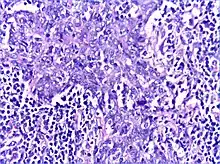

Histology

There is a marked lymphoplasmacytic infiltration. Lymphoid follicles surround solid epithelial nests, giving rise to the 'epimyoepithelial islands', that are mainly composed of ductal cells with occasional myoepithelial cells. Excess hyaline basement membrane material is deposited between cells, and there is also acinar atrophy and destruction.